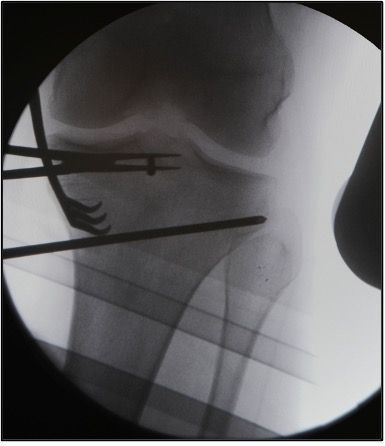

Determination of the osteotomy plane with 2 K-wires.

A first K-wire (3.0) is inserted under image intensifier monitoring from the dorsal superior margin of the pes anserinus to the superior margin of the tibiofibular joint. In order to be able to expose the tibiofibular joint, the knee is brought to 30° IR. The intraosseous length of the K-wire is measured at the same time.

A second K-wire (3.0) is positioned further anterior under image intensifier control so that the two wires are exactly superimposed. This requires that the lateral tibia plateau in the AP image only shows one line. Thus, the osteotomy plane matches the natural tibia slope in the lateral view (Fig. 5a). Thereafter, the length of the two wires is determined (ventrally usually about 10 mm shorter than dorsally).

Placement of parallel K-wires for intraoperative control of the tibial slope and rotation

Now a third K-wire (3.0) is introduced centrally in the proximal tibia with neutral rotation (patella in the center). At the same time, the knee should be flexed under image intensifier control so that the lateral tibia plateau appears as one line. This K-wire now has to appear in the image intensifier as a dot and is thus parallel to the tibial slope (Fig. 5 b).

After predrilling, a fourth K-wire (3.0) is inserted parallel to the third K-wire distal to the osteotomy surface on the anterior tibia (Fig. 5 b). Together with the third K-wire this fourth K-wire permits control of tibial slope and rotation change during the operation.